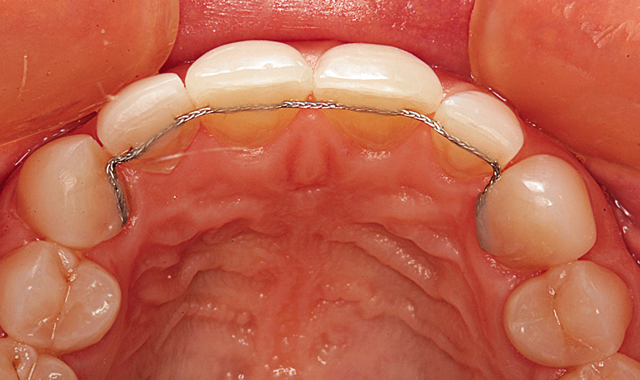

The final result can be seen from the retracted facial view in Figure 16. Bonded wire retainers were fabricated and placed. Figure 17 shows the bonded wire retainer in place for the maxillary arch and Figure 18 shows the mandibular bonded wire retainer. Mary’s new smile can be seen in Figure 19.

Fig. 18